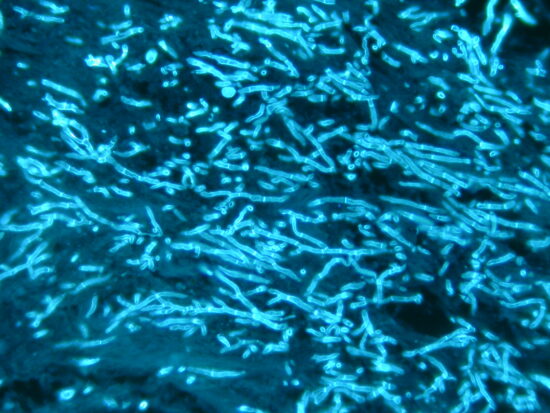

The article highlights that azole-resistant Aspergillus fumigatus is an escalating global health threat driven by both medical and agricultural azole use, leading to the emergence and environmental spread of resistant strains that undermine first-line antifungal therapies. It emphasizes that resistance arises through genetic mutations (notably in cyp51A) via two main routes—patient treatment and environmental exposure—resulting in reduced treatment efficacy and increased mortality. The paper further stresses major gaps in rapid diagnostics, surveillance, and awareness, arguing for improved detection methods, stewardship across clinical and agricultural sectors, and coordinated One Health strategies to contain the spread and safeguard future antifungal effectiveness.